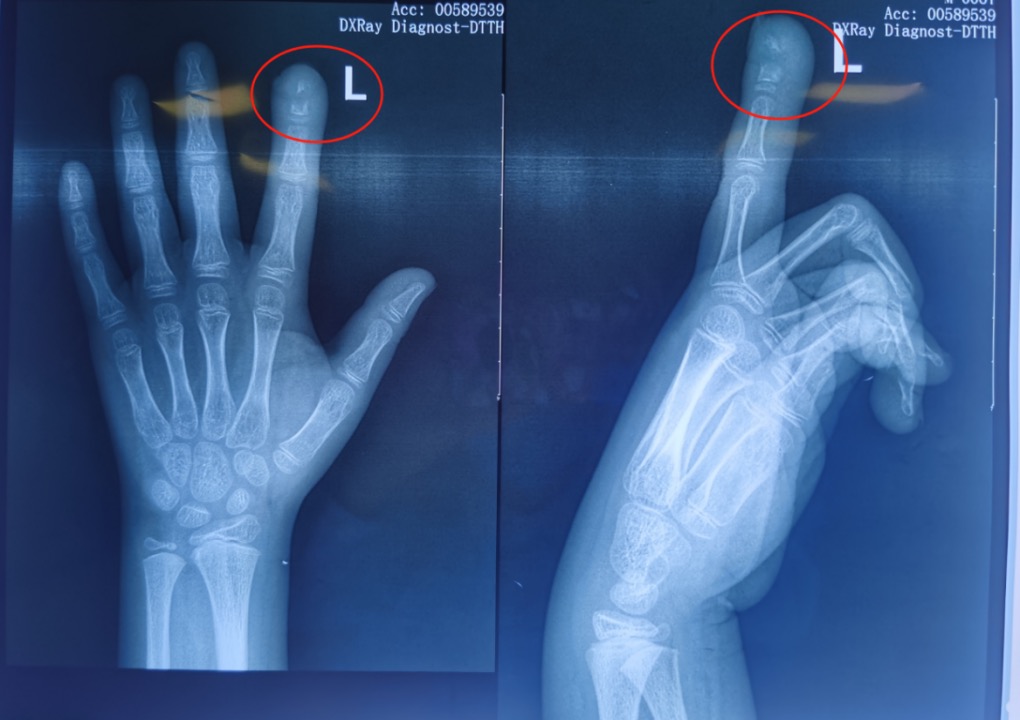

李女士再次带着奇奇去医院就诊时,X线片显示感染已经累及指骨——远节指骨大面积骨质破坏了。焦急的李女士赶紧带孩子来到湖南省儿童医院骨科进一步治疗。

△奇奇的食指远节指骨出现虫蚀样骨破坏

在湖南省儿童医院,奇奇被确诊为左手食指远节骨髓炎。湖南省儿童医院骨科主治医师熊欣介绍,目前奇奇正在接受抗感染治疗,感染控制以后再考虑二期处理病理性骨折,并且填充骨缺损的部分。